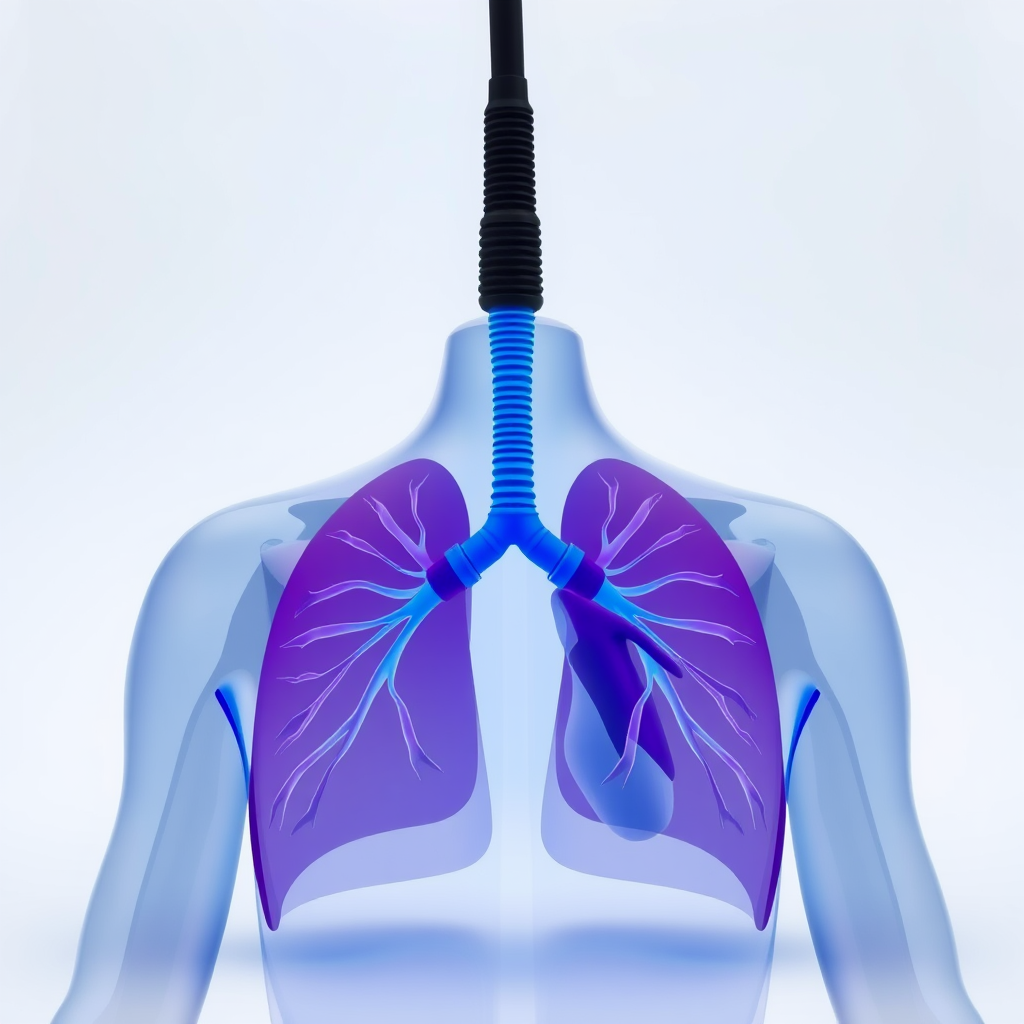

Melhora da circulação sanguínea

A fisioterapia para hipertensos em São Paulo é eficaz na melhora da circulação.

Uma circulação adequada contribui para o equilíbrio da pressão arterial.

Os exercícios estimulam a dilatação dos vasos sanguíneos, facilitando o fluxo.

Redução da pressão arterial

Um dos principais objetivos da fisioterapia para hipertensos em São Paulo é auxiliar na redução da pressão arterial.

Exercícios aeróbicos e respiratórios fazem parte do plano terapêutico.

Essas práticas contribuem para o controle dos níveis pressóricos.